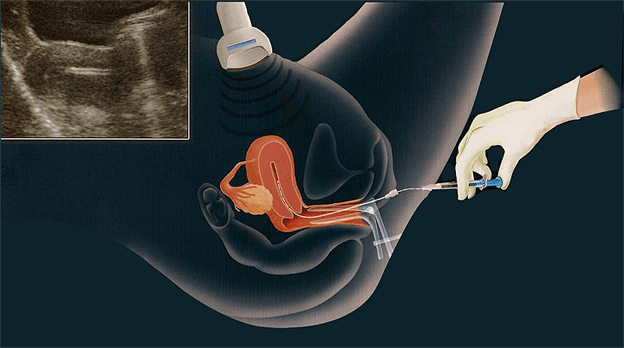

O preparo do útero costuma demorar de 15 a 18 dias (dependendo inclusive do tempo de evolução dos embriões 3 ou 5 dias), e é feito através do uso de hormônios geralmente em comprimidos orais e via vaginal. É um preparo bem mais tranquilo do que a estimulação dos ovários, além de não ser necessário uso de medicação injetável.

A transferência dos embriões para o útero é um procedimento indolor e bastante tranquilo. Não costuma levar mais do que 10 minutos e não precisa de anestesia. Nele a mulher deve estar com a bexiga cheia, o que possibilita ao médico visualizar a injeção dos embriões dentro do útero, escolhendo um local adequado. Isso incomoda um pouco. De resto, o procedimento é bastante semelhante à coleta de um Papanicolau para a mulher.

Após a transferência um exame de gravidez a ser realizado 9 ou 12 dias depois do procedimento (dependendo do tempo de evolução dos embriões de 3 ou 5 dias) informará o sucesso ou não do tratamento.